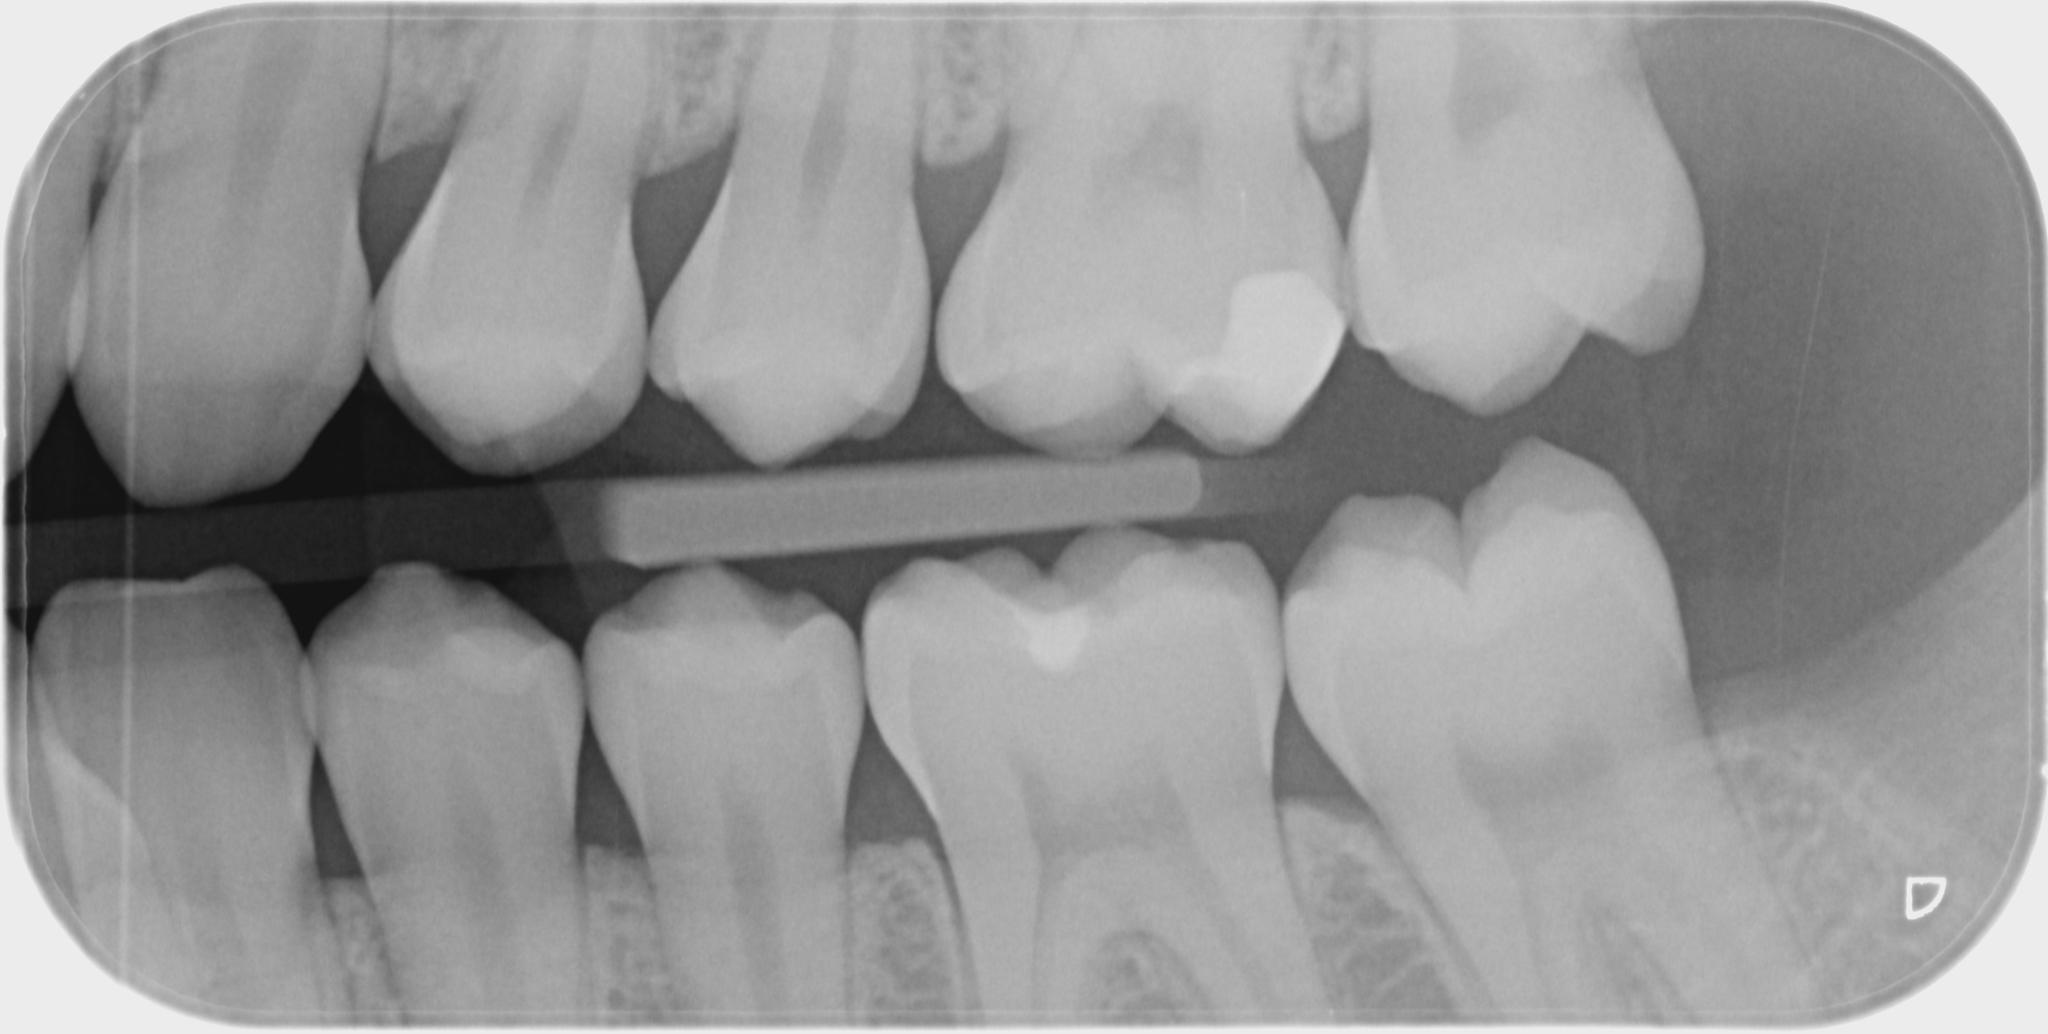

- Bissflügelaufnahme sind unerlässlich bei der Kariesdiagnostik. Die Zahnreihen der Ober- und Unterkieferseite einer Gesichtshälfte sind zu diagnostizieren. Die Zahnärzte von Medicus Dental am Schaffhauserplatz in Zürich empfehlen alle ein bis zwei Jahre regelmässige Röntgenkontrollen, um frühzeitig Karies zwischen den Zähnen zu erkennen und zu therapieren.

Ein Beispiel für eine Bissflügelaufnahme, bei gesunden Zähnen.